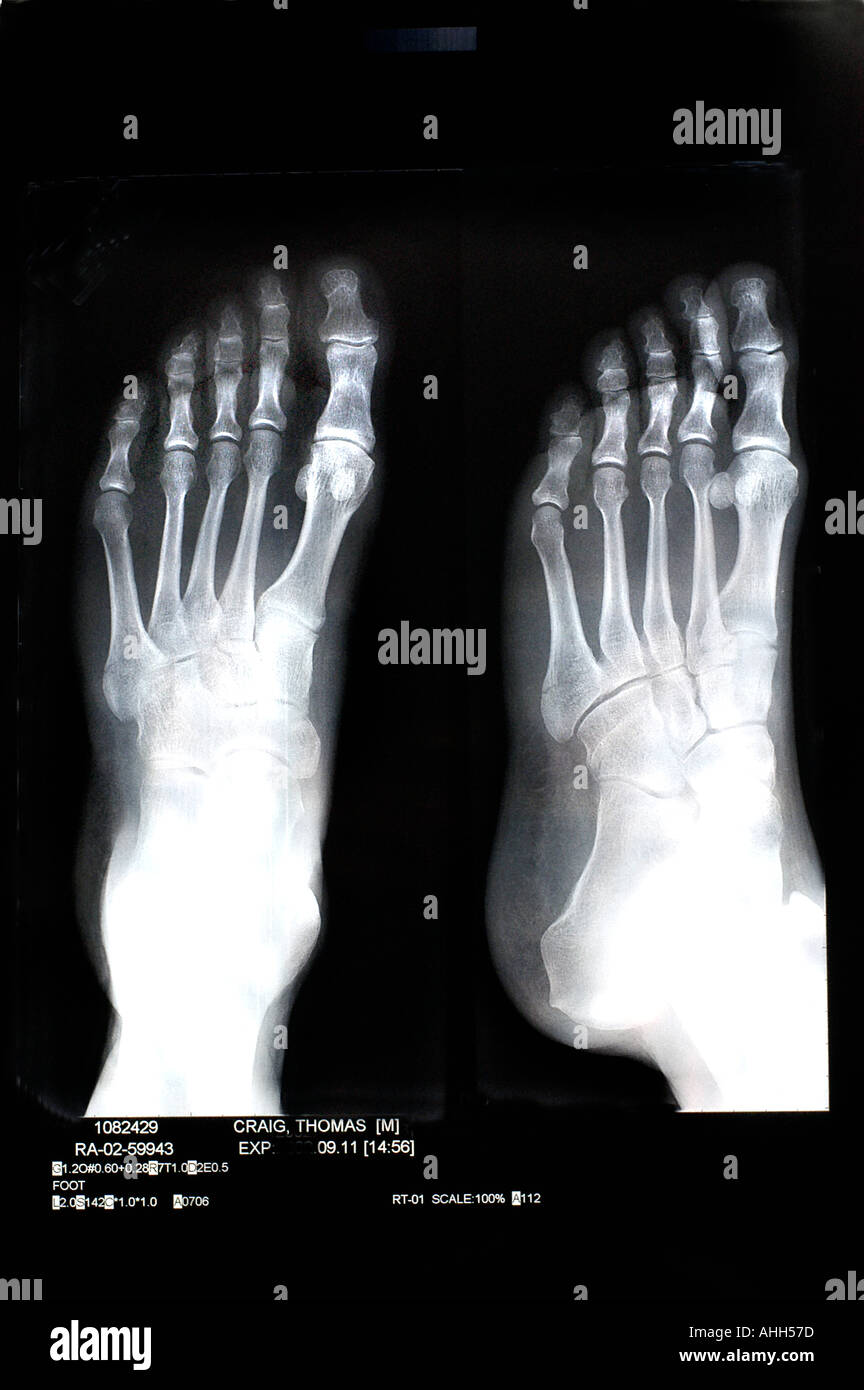

From www.alamy.com

Foot bones x rays High Resolution Stock Photography and Images Alamy Foot Bones Xray Anatomy The image displays the soft tissues and bones of your. what is foot radiograph? this view is useful in the assessment for joint abnormalities, determining the degree of dorsal or plantar displacement in fractured. Injuries to the bones of the foot commonly occur in athletes and active individuals. Anatomically the foot can be divided into the forefoot (metatarsals. Foot Bones Xray Anatomy.